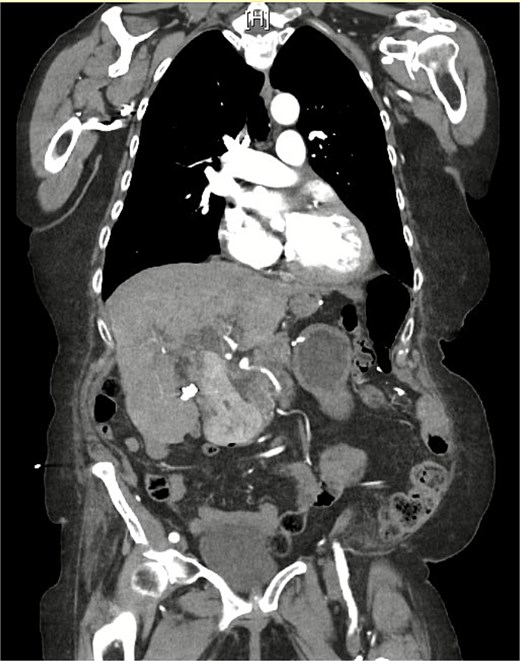

On examination, she was afebrile and hemodynamically stable. Her abdomen was mildly distended with epigastric tenderness and firmness. Laboratory workup revealed moderate leukocytosis (13.3 × 109/l), elevated lipase (288 U/l), and normal total bilirubin (0.8 mg/dl). Contrast-enhanced computed tomography (CT) demonstrated distention of the remnant stomach, duodenum (biliopancreatic limb), CBD, and intrahepatic ducts. A 9.0 × 3.4 cm heterogeneous mass was visualized in the duodenum, consistent with an obstructing gallstone (Figs 1–3).

(a and b) CT demonstrating gallstone in D3-D4 with BPD limb obstruction.